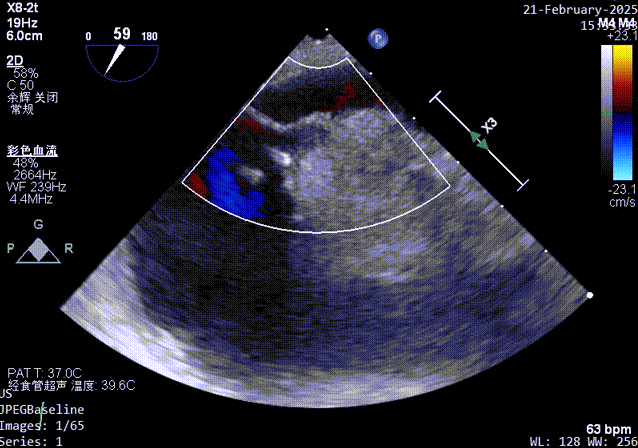

color超声影像

器械进入前TEE彩超影像

锁结操作完成后彩超影像